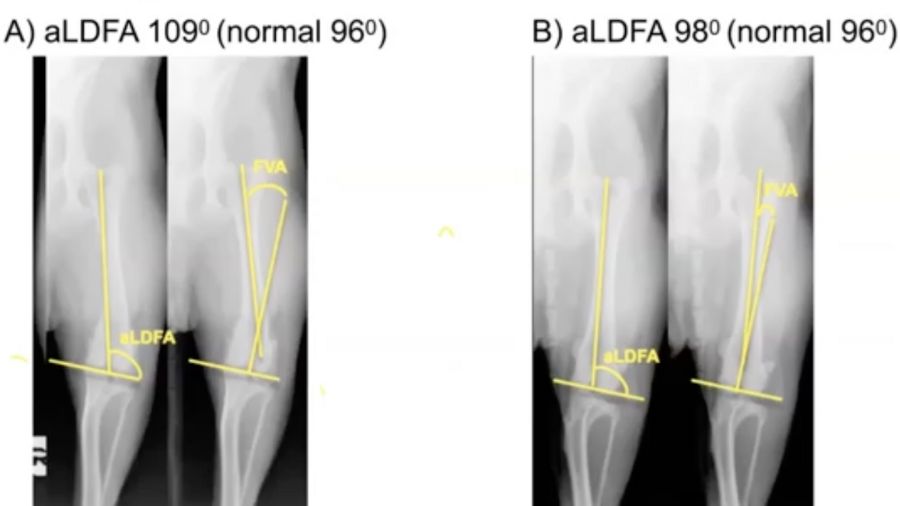

A word of caution, however. Have a look at the two cases in (Fig 4, 7:51). The image on the left has an aLDFA of 109, which is quite a big increase on the normal value of 96. The image on the right has an aLDFA of 98. You can probably already tell that these are actually the same dog and it's the radiographic positioning that is wrong – because you need to ensure that the femur is perpendicular to the beam and that the condyles bisect the fabellae.